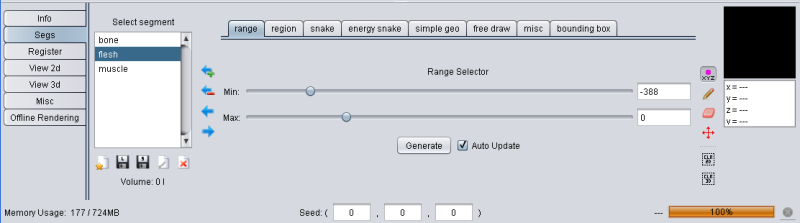

To create a segment different segmentation methods can be used and even combined. The second tab in the tool pane (labeled "Segs") contains the tools to create, delete and manage segments.

Complex structures such as the human brain can usually be not segmented with a single segmentation method, YaDiV uses a managed segmentation concept: Each segmentation method selects voxel in a "temporary segment", which can be added to (or removed from) a "real" segment. This way it is possible to combine several segmentation methods.

The temporary selection is always drawn in red. For example, if you have a blue segment wich overlaps with the current selection, the overlapping region will be drawn in purple since red + blue = purple. To make things easier to see, a simple geometric shaped blue segment is used (sphere) and the temorary segment/selection is shaped like a small red box.

Range based segmenting is a very simple but often used segmentation method. With a given minimum and maximum value, it segments all voxels with values in that range. In YaDiV you can use the sliders to define min and max or enter the value directly in the textfield.